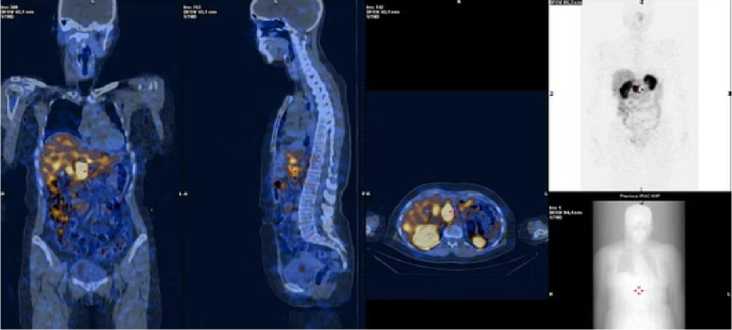

Через 2 мес. по завершении циклов ПРРТ у 1 одной пациентки (G3) отмечалась стабилизация метастатического процесса в печени при исходном градировании по шкале NETPET – 2b, у 17 пациентов (G1 – 8, G2 – 8, G –1) регистрировалась картина частичного ответа (рис. 3, 4) при показателях NETPET 1-2a, а у 3 пациентов (G1 – 1 и G2 – 2) – полный структурный ответ на ПРРТ при исходном градировании по шкале NETPET равном 1. Ни у одного из пациентов не зарегистрировано нарушения функции почек, проанализированное по уровню креатинина к моменту завершения терапии 177Lu-DOTA-TATE, что говорит об отсутствии значимой подострой нефротоксичности (табл. 2).

Рис. 3. ОФЭКТ/КТ пациентки Б., с метастатическим поражением печени при НЭО после первого введения 177Lu-DOTA-TATE: множественные мтс-очаги в печени.

Рис. 4. ОФЭКТ/КТ пациентки Б., с метастатическим поражением печени при НЭО после

6 введений 177Lu-DOTA-TATE (Асумм.=39,7 ГБк): исчезновение множественных мтс-очагов в печени, единичный мтс-очаг в левой доле. Картина частичного ответа на лечение.